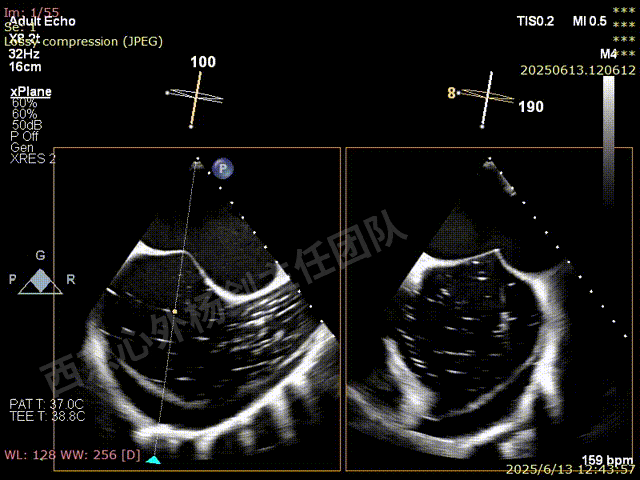

二尖瓣后叶栓系严重,前叶相对错位,反流束沿2区分布广泛,2偏3区处存在反流。

反流宽度至少23mm,因影像调整困难,考虑实际反流更宽。